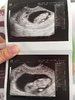

Ja już po wizycie wszystko ok dzidziol ma ponad 3 cm i ma się dobrze ;) śmieje się ze grubasek mały jest ;)

IMG_0876.JPG

• IMG_0876.JPG

226,4 KB · Wyświetleń: 332